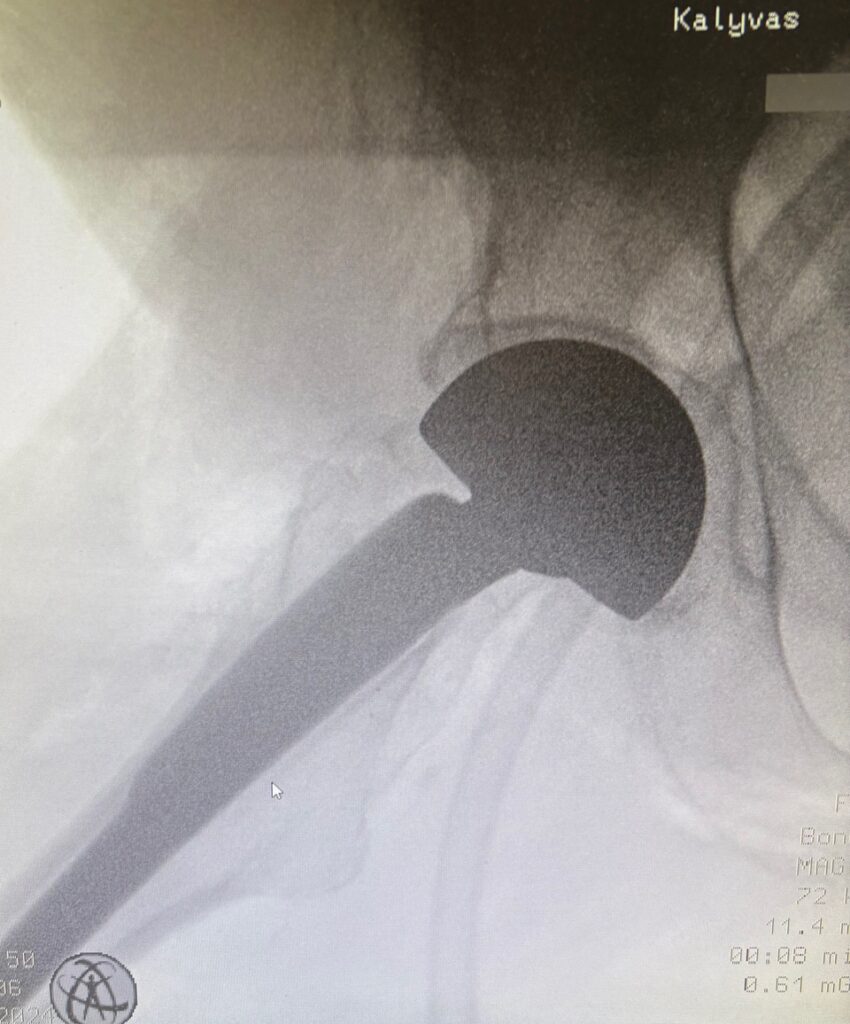

Η ημιολική αρθροπλαστική ισχίου είναι μια αξιόπιστη χειρουργική επέμβαση που εφαρμόζεται σε κατάγματα του αυχένα του μηριαίου οστού, ιδιαίτερα σε ηλικιωμένους ασθενείς ή σε άτομα με χαμηλότερες λειτουργικές απαιτήσεις. Κατά την επέμβαση αντικαθίσταται μόνο η κεφαλή του μηριαίου, ενώ διατηρείται η φυσική κοτύλη. Στόχος είναι η άμεση ανακούφιση από τον πόνο, η μικρή απώλεια αίματος, η γρήγορη κινητοποίηση και η ταχεία επάνοδος του ασθενούς στην καθημερινή λειτουργικότητα, με ασφάλεια και καλά μακροπρόθεσμα αποτελέσματα.

Η ημιολική αρθροπλαστική ισχίου με την ελάχιστα επεμβατική τεχνική AMIS (Anterior Minimally Invasive Surgery) αποτελεί σύγχρονη χειρουργική επιλογή. Η επέμβαση πραγματοποιείται από πρόσθια προσπέλαση, χωρίς διατομή μυών, γεγονός που συμβάλλει σε μικρότερο μετεγχειρητικό πόνο, ταχύτερη αποκατάσταση και άμεση κινητοποίηση του ασθενούς. Η τεχνική AMIS επιτρέπει υψηλή ακρίβεια τοποθέτησης της πρόθεσης και μειώνει τον κίνδυνο εξαρθρήματος, προσφέροντας ασφαλή και αξιόπιστα λειτουργικά αποτελέσματα.

Ο έμπειρος ορθοπαιδικός χειρουργός κ. Νικόλαος Καλύβας εφαρμόζει την Ημιολική Αρθροπλαστική Ισχίου με τεχνική (AMIS) επί σειρά ετών στη Γερμανία, έχοντας χειρουργήσει μεγάλο αριθμό ασθενών. Τα τελευταία χρόνια, από τη θέση του Αναπληρωτή Διευθυντή σε ένα από τα μεγαλύτερα κέντρα αρθροπλαστικής της Γερμανίας, είχε ενεργό ρόλο στην εκπαίδευση ειδικευομένων ορθοπαιδικών στη συγκεκριμένη τεχνική.